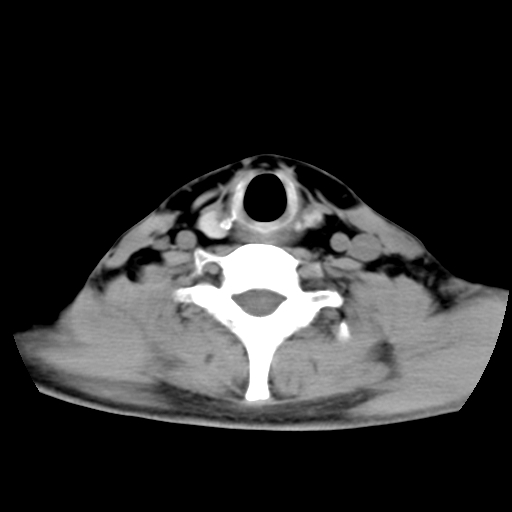

标题: CT24019:男,45岁,发现颈部肿物5个月。 [打印本页]

男,45岁,发现颈部肿物5个月,彩超示:双侧颈部及下颌部软组织增厚。

考虑双侧颈项部良性对称性脂肪增多症。